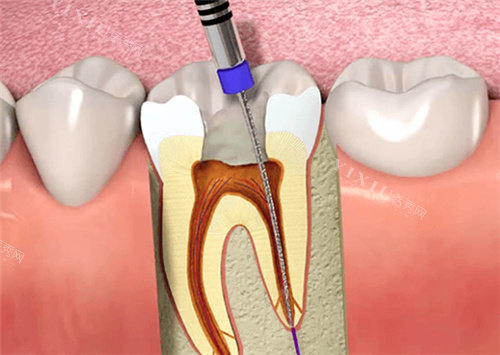

二、补牙修复项目全攻略

3M Z350树脂补牙:150元起(单颗),进口纳米树脂,耐磨性强,颜色自然。

美学嵌体修复:800-1500元/颗,CAD/CAM智能化制作,比较准贴合牙体形态。